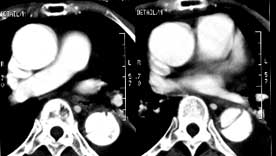

女性,71岁,胸骨后疼痛两小时来诊。体检:心界左下扩大,心率70次/每分,律齐,无杂音。x线胸片示:纵隔增宽。

ct平扫:降主动脉全程约18cm范围内管腔扩张,管腔被条索影分隔成前内、外后两腔,条索影与管壁连接处见散在点状钙化影。

增强扫描:见前内腔较小,与主动脉弓同步强化;后外腔较大,造影剂消退时间教主动脉弓延长,切管壁不均匀增厚,强化不明显。

ct诊断:降主动脉夹层动脉瘤,伴附壁血栓形成。